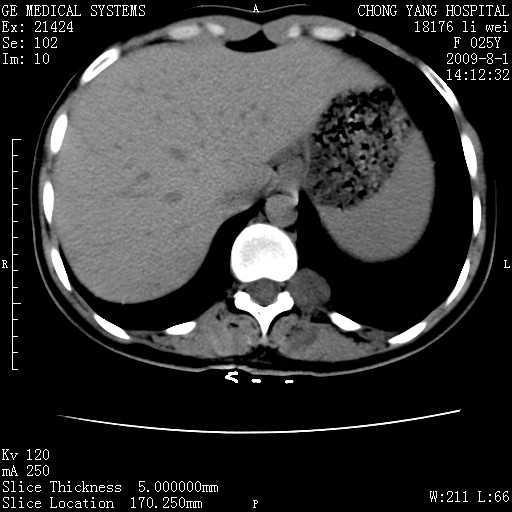

以下是引用pujunzhi在2009-8-1 20:23:00的发言:[br]胸椎旁及背部肌间良性病变,范围广,边界清,沿肌间生长,考虑淋巴管瘤、血管瘤,建议增强扫描。